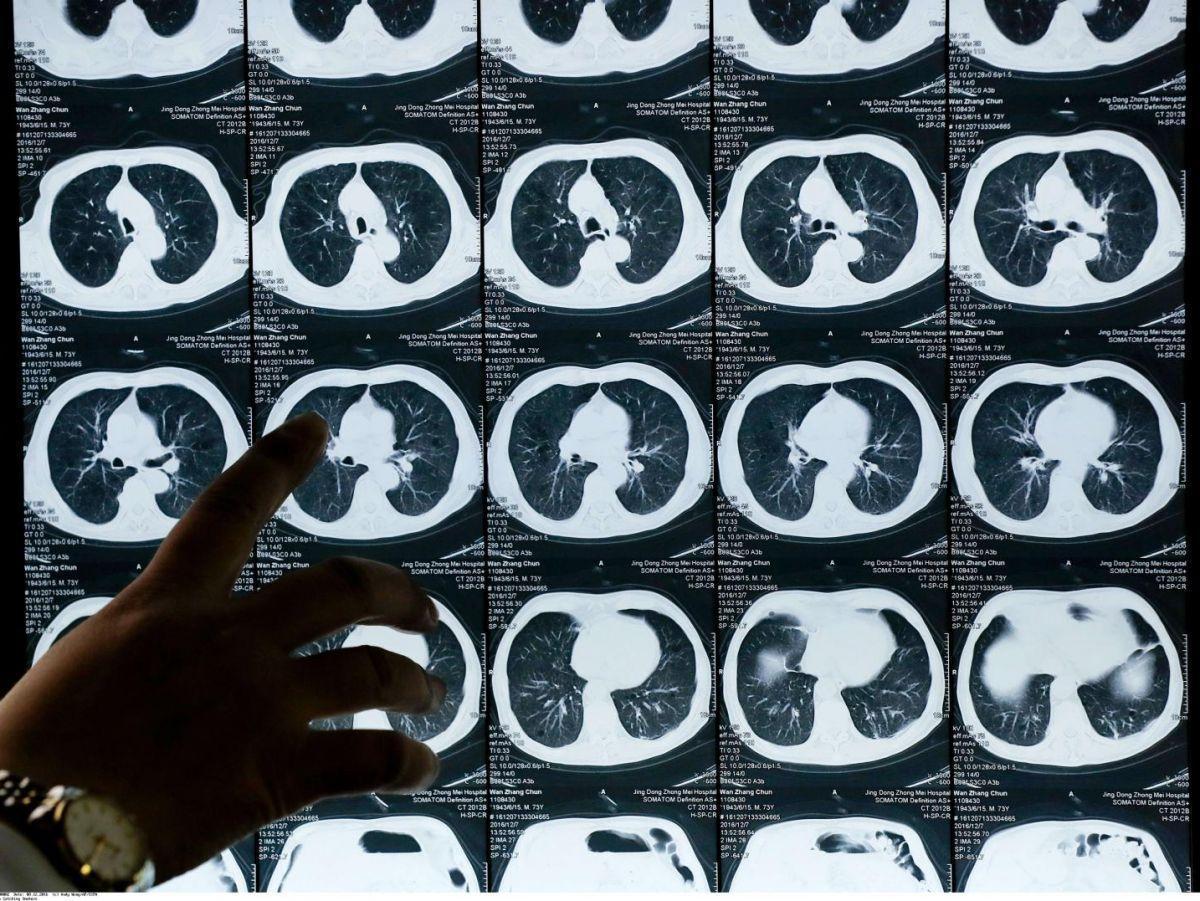

Un traitement pour les patients atteints de la forme la plus commune de cancer du poumon

Cette annonce orale a été de plus accompagnée par une publication simultanée dans le New England Journal of Medicine, ce qui vient évidemment renforcer l’importance de son résultat. Elle concerne les patients atteints d’un cancer dit “non à petites cellules”, la forme la plus commune de ce type de cancer, présentant un type particulier de mutation, dit de type Egfr, soit environ 10 % à 25 % des patients aux États-Unis et en Europe, 30 % à 40 % en Asie.